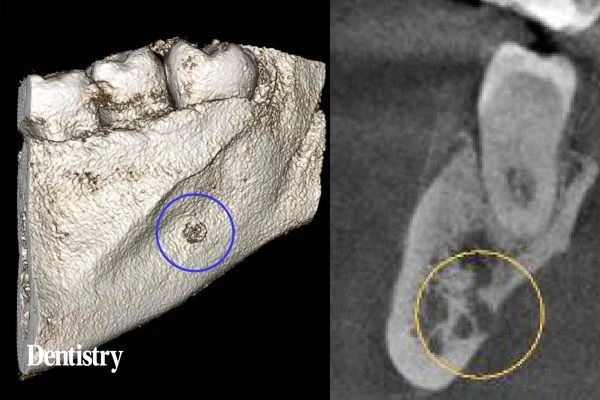

Ở mảng vỏ xương bên dưới răng cối số 7 hàm dưới là một lỗ được xác định rõ. Lỗ này rộng 4mm, mất mặt ngoài của mảng vỏ xương với khoảng tủy xương. Nó rất gần với ống thần kinh hàm dưới. Kèm theo là tình trạng viêm của nó có thể gây đau.

Hiếm khi, một phát hiện như hình ảnh X-quang ở vùng răng cối số 7 hàm dưới có thể là một tổn thương nghiêm trọng như đa u tủy. Khi đó việc theo dõi thêm sẽ được khuyến nghị với bác sĩ phẫu thuật răng miệng.